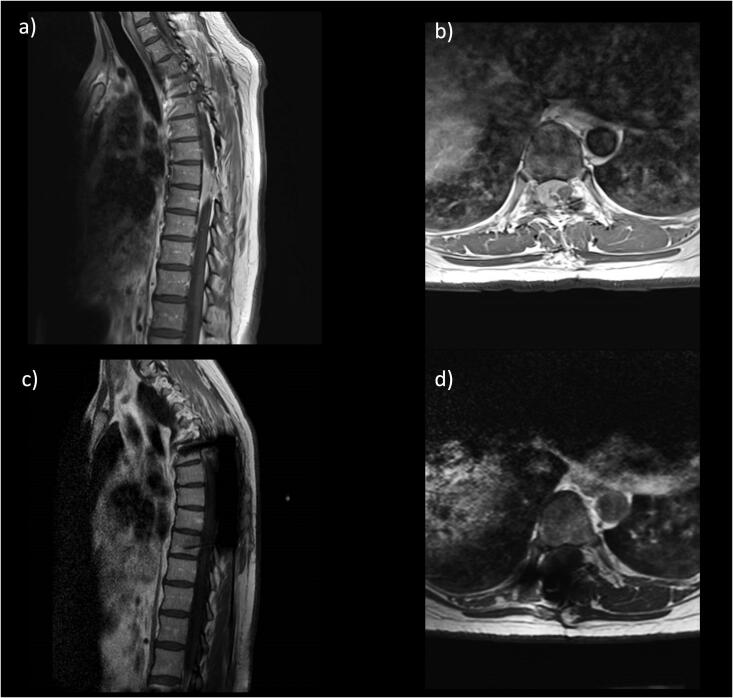

目的:脊髓脑脊液(CSF)漏是一种常见病,其治疗方法多种多样。对于高流量漏,许多研究都主张进行硬脑膜修复和 CSF 分流。LiquoGuard7® 可以自动、精确地控制压力和容量,并计算患者特定的 CSF 产出率 (prCSF):本单中心病例系列包括接受复杂脊柱手术的患者,这些患者的情况如下:1) 预计术中和/或术后会出现高流量 CSF 渗漏;2) 使用 LiquoGuard7® 进行腰椎 CSF 引流。为每位患者量身定制了 CSF 引流方案,并结合分层脊柱伤口闭合术:结果:共纳入三名患者,病理类型各异:结果:共收治了三名患者,他们患有不同的病症:T7/T8 椎间盘脱出、T8-T9 脑膜瘤和 T4-T5 转移性脊髓压迫。前两名患者接受了 CSF 转移术,以防止术后 CSF 渗漏,而第三名患者则因术后 CSF 渗漏而需要接受 CSF 转移术。所有病例的 CSF 都明显分泌过多(平均 >/=140 毫升/小时)。根据患者的具体情况制定脑脊液引流方案后,没有病例因脑脊液瘘修补(包括胸腔积液)、伤口破裂或感染而需要进一步干预:结论:患者特异性脑脊液引流可能是治疗复杂脊柱手术中术中和术后高流量脑脊液漏的有效工具。这些系统可减少术后从伤口或邻近体腔漏出的 CSF。需要进一步开展更大规模的研究,以评估这种方法的比较效益和成本效益。

Results: Three patients were included, with a variety of pathologies: T7/T8 disc prolapse, T8-T9 meningioma, and T4-T5 metastatic spinal cord compression. The first two patients underwent CSF diversion to prevent post-op CSF leak, whilst the third required this in response to post-op CSF leak. CSF hyperproduction was evident in all cases (mean >/=140ml/hr). With patient-specific CSF diversion regimes, no cases required further intervention for CSF fistulae repair (including for pleural CSF effusion), wound breakdown or infection.